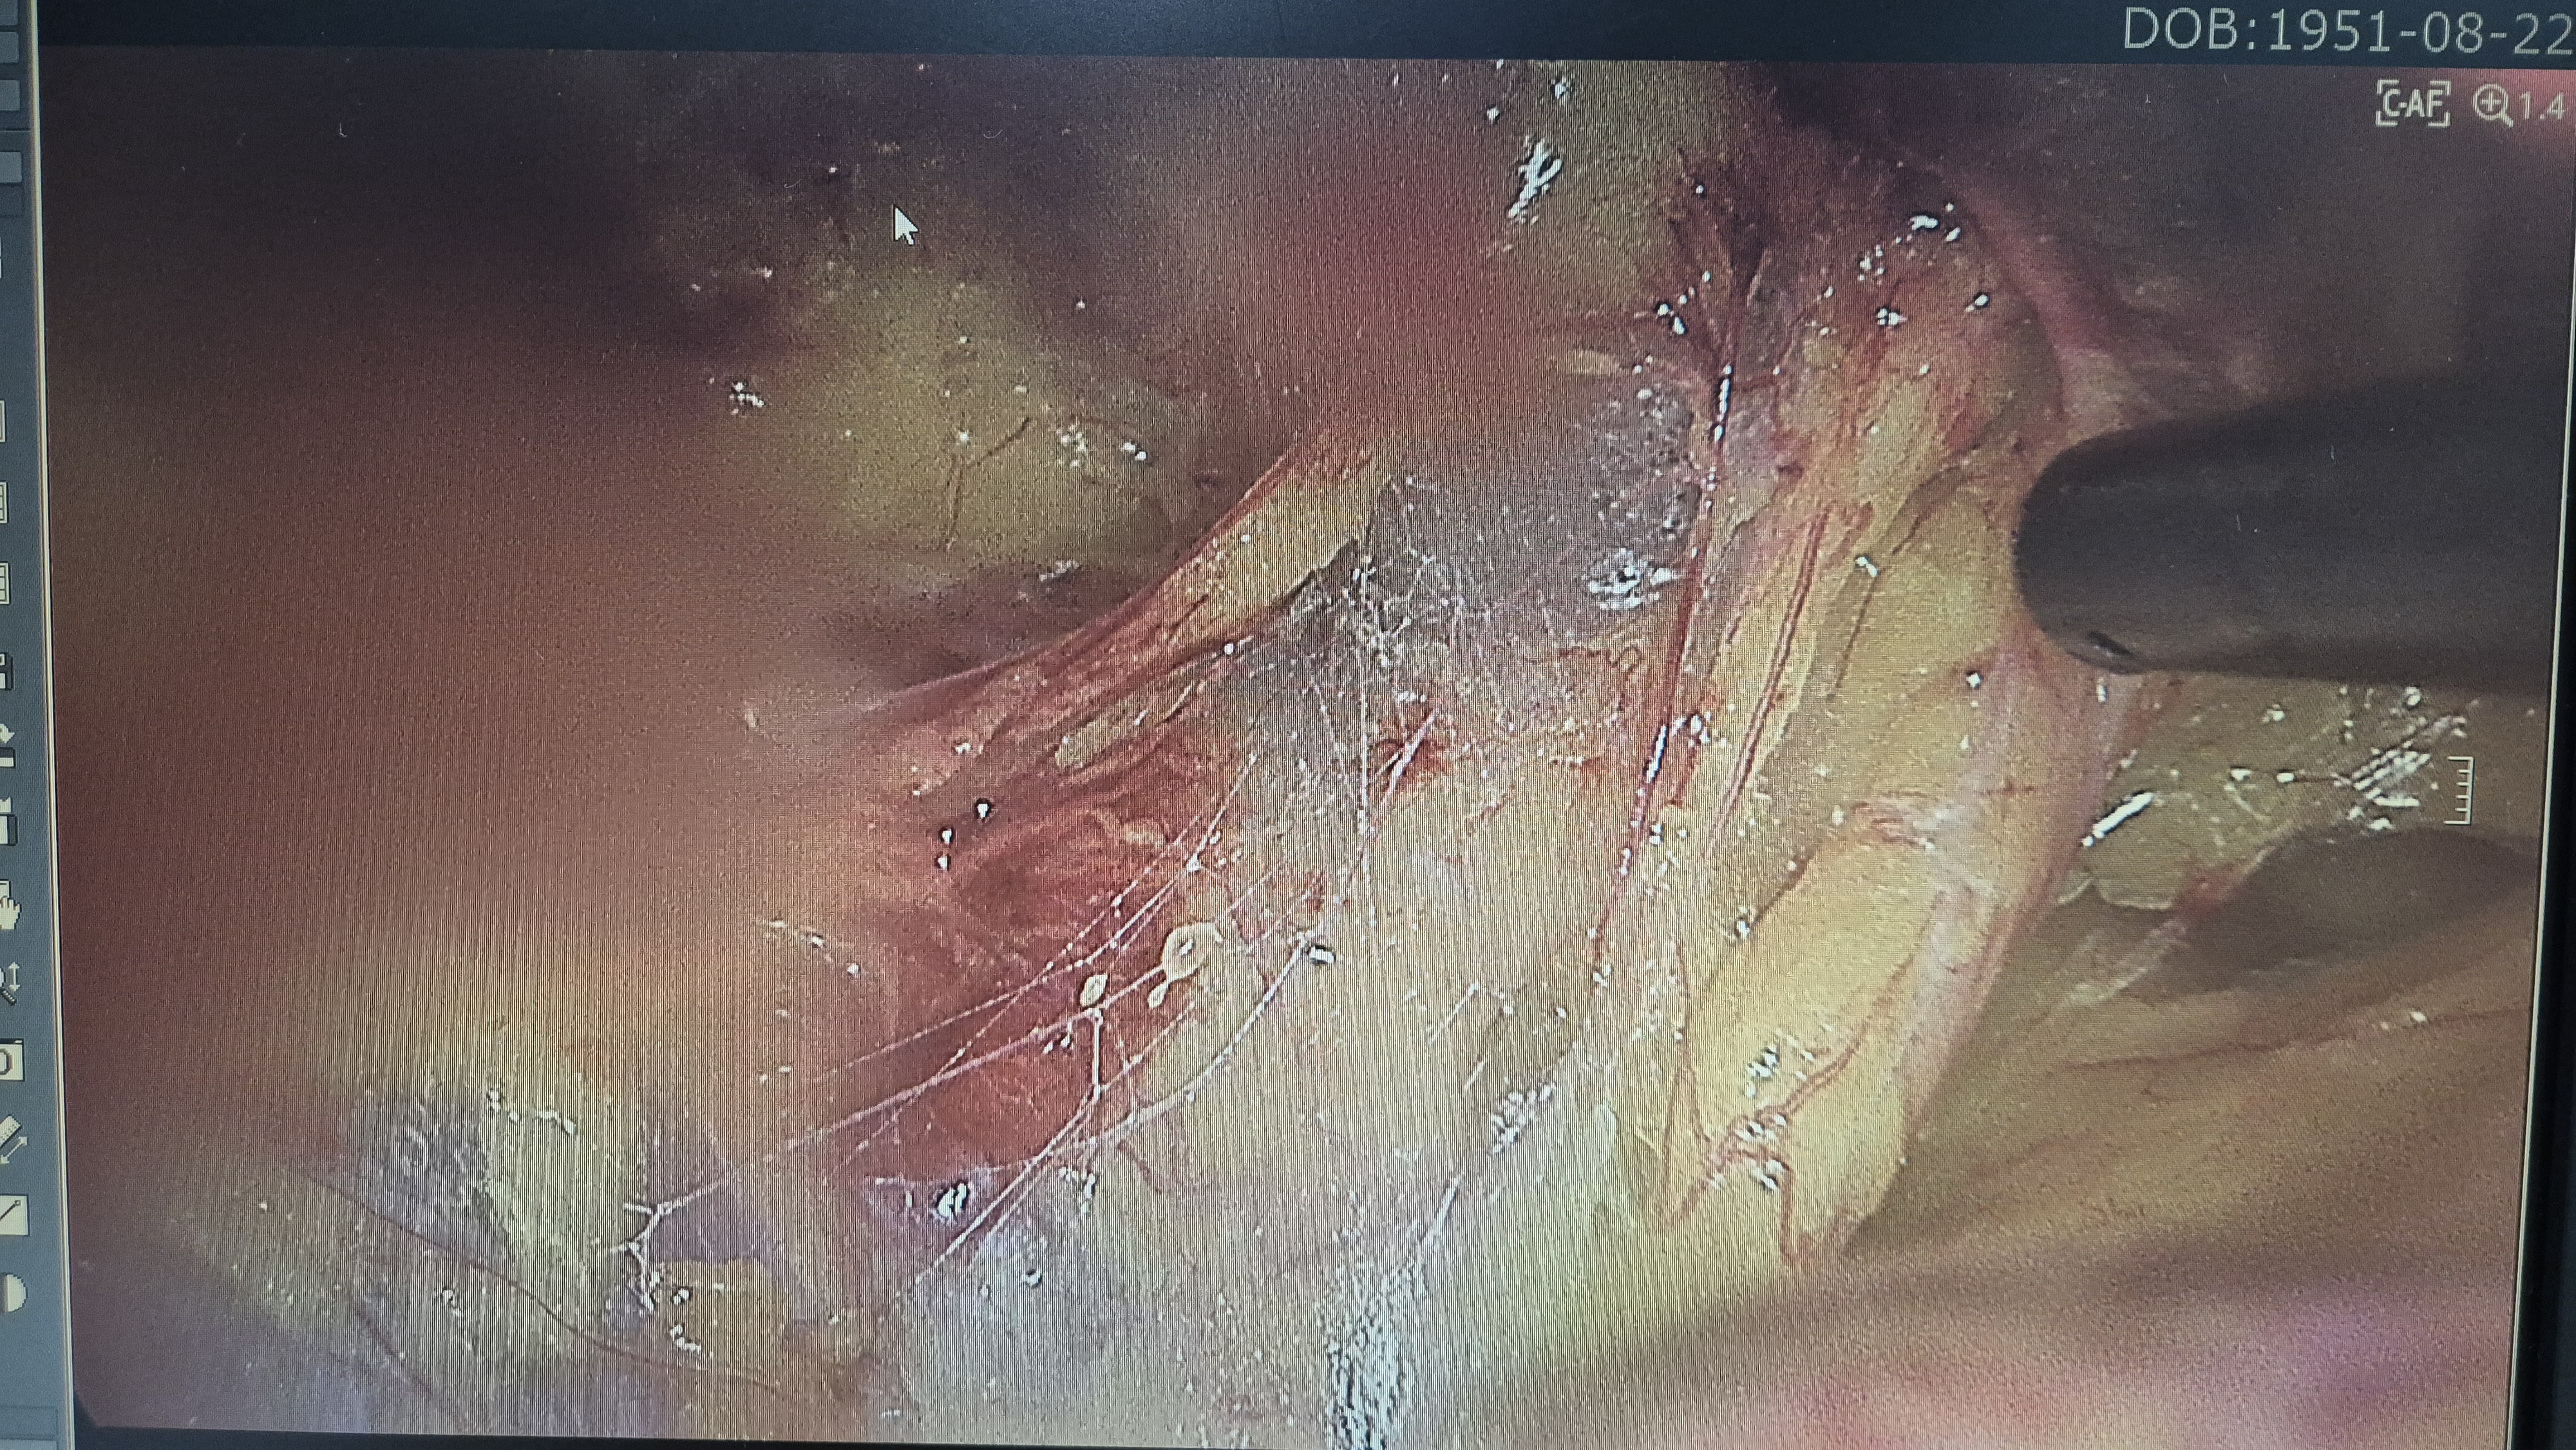

탈정 확인.

박리후.

메쉬로 고정.